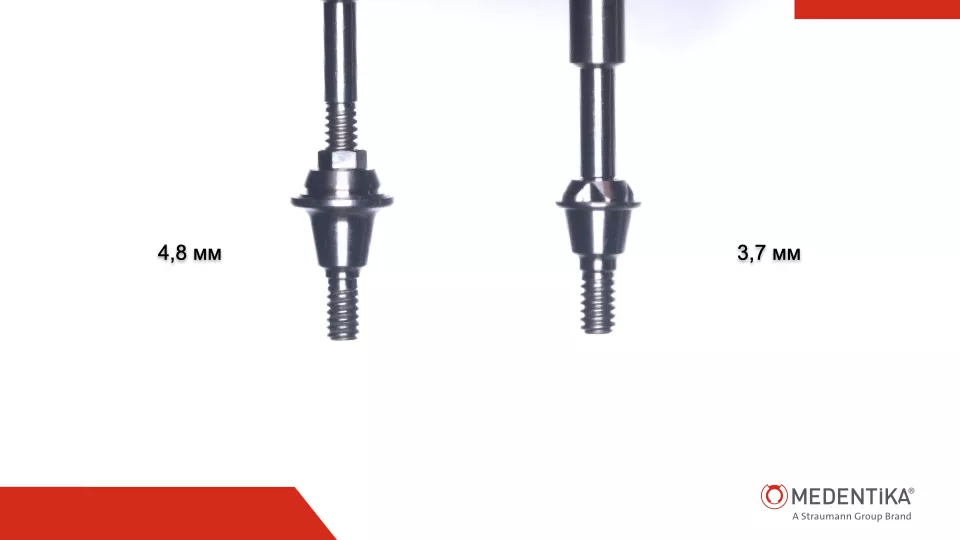

На конечном этапе протезирования была определена необходимость углубить расположения ортопедических элементов для создания более плавного выхода коронок и тем самым изготовление более гигиенически обслуживаемой конструкции.

Задача была получить соединение на меньшей высоте и с более узкого основания.

Эту задачу удалось выполнить благодаря MedentiBase, диаметр которого уже на 1.1 мм чем у MultiUnit абатмента, а высота имеет вариабельность от 0,5 до 4.5 мм, с шагом в 1 мм (Илл. 41).

Сравнение MultiUnit абатмента и MedentiBase абатмента в полости рта (Илл. 42-49).